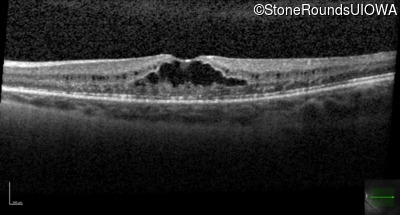

Optical Coherence Tomography - Left - 20/50

Exemplar / OCT Stack

OCT Stack